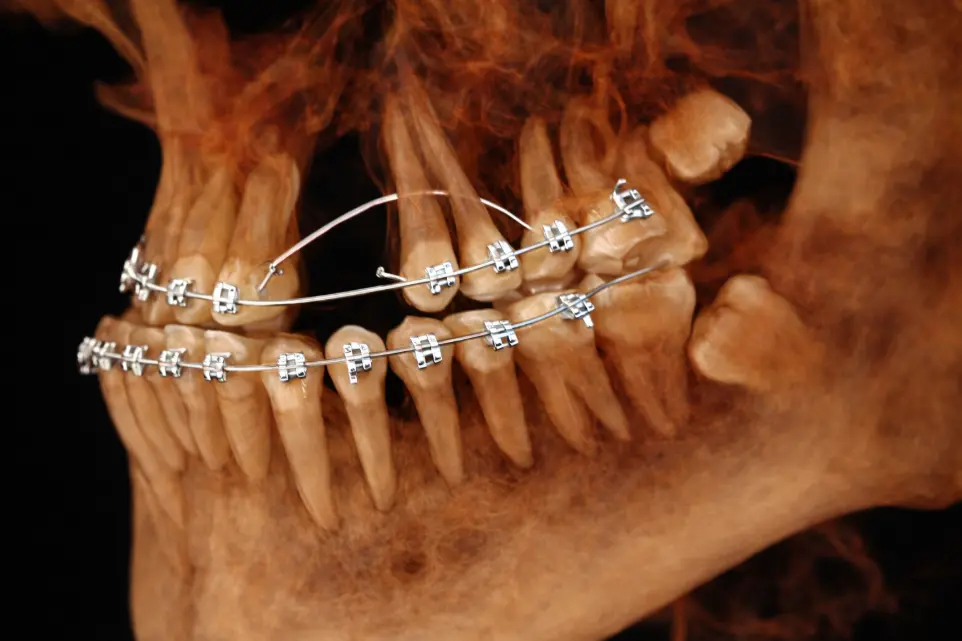

TOMOGRAFÍA PARA PLANIFICACIÓN DE MARPE

Evalua el estadio de la sutura intermaxilar y condiciones óseas del hueso palatino.